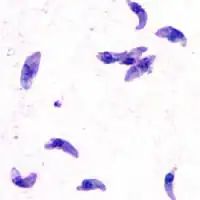

| Giemsa stained T. gondii tachyzoites, 1000× magnification | |

Tachyzoites

Motile, and quickly multiplying, tachyzoites are responsible for expanding the population of the parasite in the host.[47][30]: 19 When a host consumes a tissue cyst (containing bradyzoites) or an oocyst (containing sporozoites), the bradyzoites or sporozoites stage-convert into tachyzoites upon infecting the intestinal epithelium of the host.[30]: 359 During the initial acute period of infection, tachyzoites spread throughout the body via the blood stream.[30]: 39–40 During the later, latent (chronic) stages of infection, tachyzoites stage-convert to bradyzoites to form tissue cysts. To survive in the host, tachyzoites manipulate the immune response by injecting the contents of rhoptries into host cells. This seems to be vital for their survival, as knock-out strains of T. gondii which are unable to inject hosts with rhoptries have been shown to be avirulent in vivo.[29]